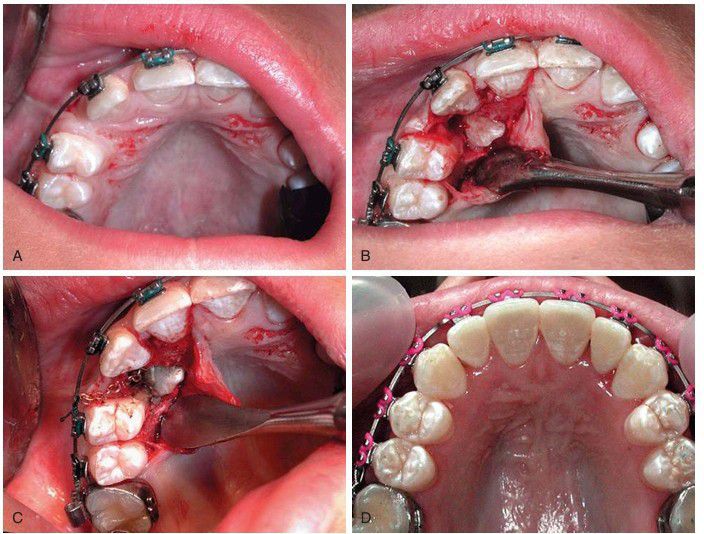

(A) Labially positioned impacted maxillary canine. The tooth should be uncovered with an apically positioned flap procedure to preserve the attached gingiva. (B) The mucoperiosteal flap is outlined, allowing for repositioning of the keratinized mucosa over the exposed tooth. When the flap is reflected, the thin overlying bone is removed. (C) The tissue is retracted and bracket bonded to the tooth with an attached gold chain. The flap is apically sutured to the tooth. (D) After 6 months the exposed tooth is in the desired position with the broad zone of the attached gingiva. (Courtesy Dr. Myron Tucker.